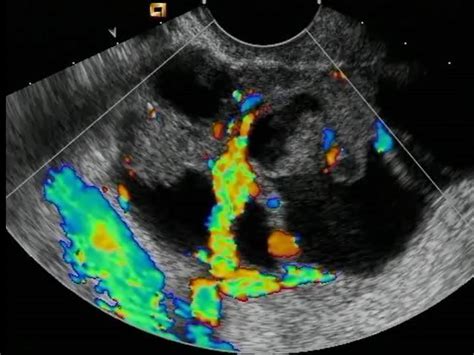

• Increased Vascularity: Using Doppler ultrasound, doctors can assess blood flow. Cancerous tumors often create their own blood supply, leading to irregular or high-velocity blood flow patterns.